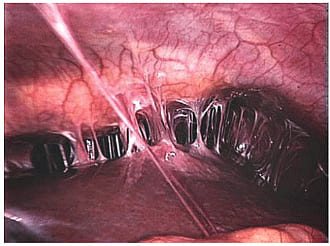

Спайки вокруг матки с вовлечением маточных труб. Спайки (синехии) внутри полости матки.

При неэффективности медикаментозного лечения хронической формы заболевания, остротекущем и интеркуррентном вариантах патологии показано хирургическое вмешательство. Для рассечения спаек обычно применяют эндоскопические операции. Зачастую лапароскопия является лечебно-диагностической процедурой, соединительнотканные сращения рассекают прямо в ходе обследования. В зависимости от применяемых инструментов такие вмешательства могут быть лазерохирургическими, электрохирургическими и аквадиссекционными. В последнем случае спайки разрушают повышенным давлением воды. При распространенном спаечном процессе выполняют альтернативные варианты лапароскопии: двойную с атипичными точками введения троакара, открытую (минилапаротомическую) с прямым введением троакара, с созданием пневмоперитонеума повышенного давления. Операции с рассечением спаек скальпелем в наши дни проводятся редко.

- Лапароскопия. Это метод не только для диагностики, но и лечения спаечной болезни. В ходе операции специальными манипуляторами, помещенным в брюшную полость, врач может проводить какие-то действия (например, рассекать спайки, формировать «заново» маточные трубы и их фимбриальный отдел, выделять из спаек яичники), но и видеть все происходящее на экране.